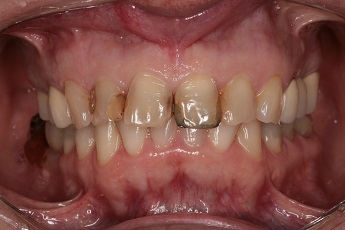

3) fotodokumentace - fotografie stavu chrupu a otisky na studijní modely

Fotodokumentace a model se provádí u pacientů s potřebou kompletní rekonstrukce chrupu.

Foto 9-13: Fotodokumentace situace v ústech - vlevo, vpravo, uprostřed, v horní a dolní čelisti.

Foto 14, 15: Vlevo zuby v úsměvu před ošetřením chrupu. Vpravo fotografie skusu zubů.

2. Klient s potřebou kompletní rekonstrukce chrupu

V tomto případě je pro lékaře obzvláště důležité provést podrobné vstupní vyšetření včetně fotodokumentace, protože tvorba terapeutického plánu probíhá za nepřítomnosti pacienta. Na základě rozboru fotografií, skusových poměrů na studijních modelech a srovnání poznatků z rentgenologického vyšetření s vlastní prohlídkou dutiny ústní jsou navrženy možné postupy ošetření s cenovým návrhem. Vše se odesílá pacientovi emailem k odsouhlasení, případně je pozván ještě na jednu konzultaci, kde se mu možné postupy vysvětlí a dohodne se, jaké řešení je ochoten akceptovat. Akceptací je myšleno např. rozhodnutí se mezi fixním a snímatelným řešením (např. implantáty versus protéza), někteří klienti nechtějí podstoupit časově náročnou léčbu zubu, u kterého nelze stanovit dobu přežití na 10 let a více, tak se i přes možnost jeho záchrany rozhodnou pro pohodlnější řešení a to zub vytrhnout a nahradit ho dentálním implantátem (jednodušší řešení se stejnou životností).